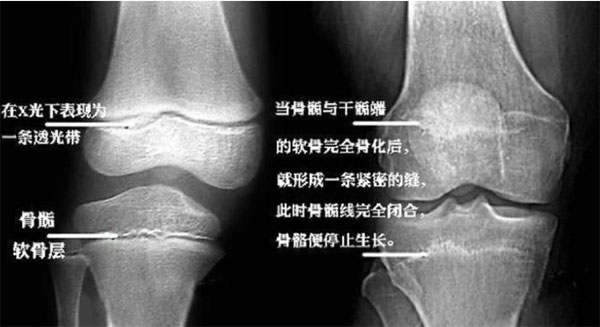

一般來說,男孩在16-18歲時骨垢線閉合,女孩在12-16歲時骨垢線閉合。